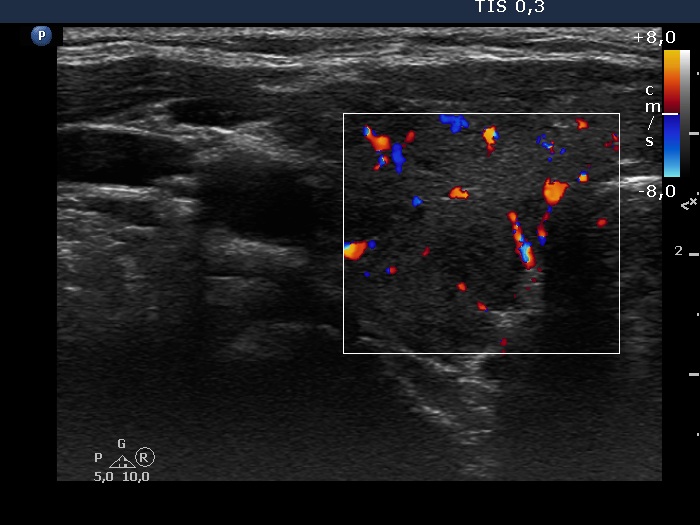

Right lobe, transverse scan, color Doppler method. The vascularization is not specific.